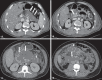

Acute pancreatitis is an inflammatory condition caused by intracellular activation and extravasation of inappropriate proteolytic enzymes determining destruction of pancreatic parenchyma and peripancreatic tissues. This is a fairly common clinical condition with two main presentations, namely, endematous pancreatitis - a less severe presentation -, and necrotizing pancreatitis - the most severe presentation that affects a significant part of patients. The radiological evaluation, particularly by computed tomography, plays a fundamental role in the definition of the management of severe cases, especially regarding the characterization of local complications with implications in the prognosis and in the definition of the therapeutic approach. New concepts include the subdivision of necrotizing pancreatitis into the following presentations: pancreatic parenchymal necrosis with concomitant peripancreatic tissue necrosis, and necrosis restricted to peripancreatic tissues. Moreover, there was a systematization of the terms acute peripancreatic fluid collection, pseudocyst, post-necrotic pancreatic/peripancreatic fluid collections and walled-off pancreatic necrosis. The knowledge about such terms is extremely relevant to standardize the terminology utilized by specialists involved in the diagnosis and treatment of these patients.